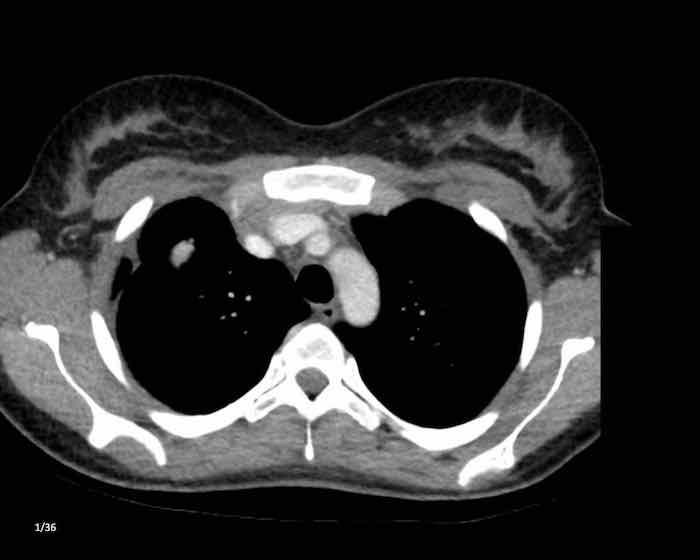

Các hình ảnh này của một nam giới 19 tuổi, được chụp CT để loại trừ thuyên tắc phổi.

Phát hiện tình cờ một khối ở khoang trước mạch máu.

Chẩn đoán có khả năng nhất là tăng sản tuyến ức và MRI được thực hiện để phân biệt thêm khối này.